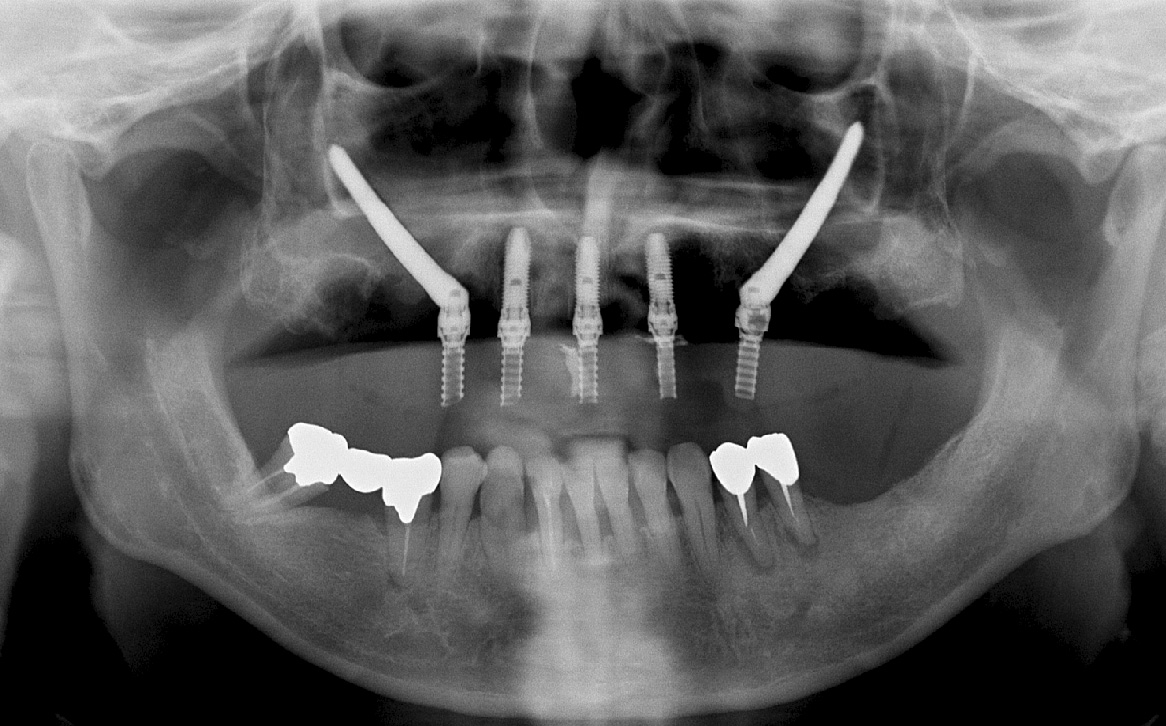

症例③オールオン4 + ザイゴマ

• Before

• After

合わない総入れ歯と歯周病がひどい部分を全部除去してオールオン4とザイゴマにて治療した症例。